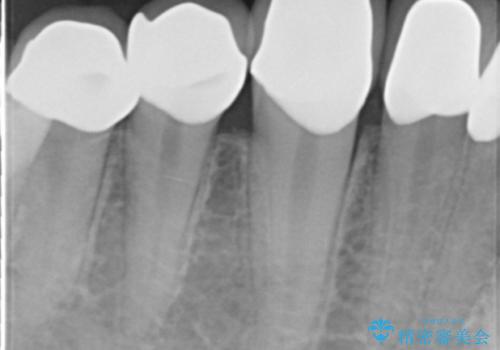

精査したところ、ほとんどの歯が保険内のレジンで充填されており、咬み合わせも悪く咬合していない歯もありました。

虫歯をしっかりと治療したのち、オールセラミッククラウンによる補綴治療を行いました。